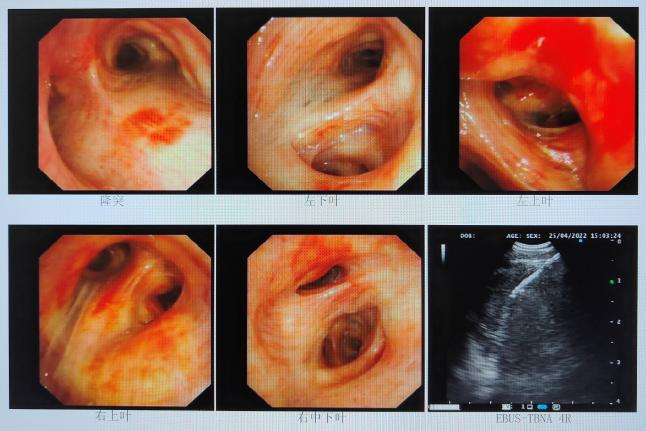

2022年4月22日支气管镜检查:1.左上叶病变:Ca?其他2.纵隔肺门淋巴结增大(EBUS探及)。病检:涂片、5/4R、7组淋巴结EBUS-TBNA;6/左上叶。